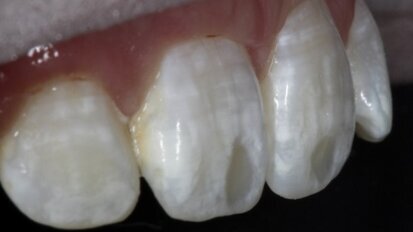

Regeneracja kości i pokrycie recesji w leczeniu estetyczno-implantologicznym

Autor prezentuje opis przypadku leczenia kompleksowego z planowaniem w centralnej relacji. Wykonano zabieg przeszczepienia pełnego bloku kostnego i ...

Odbudowa ubytku kostnego w szczęce allogennym blokiem kostnym z PRP

W pracy przedstawiono przypadek pacjentki z defektem kostnym w odcinku przednim szczęki powstałym po zabiegu ekstrakcji zęba 11, połączonym z ...